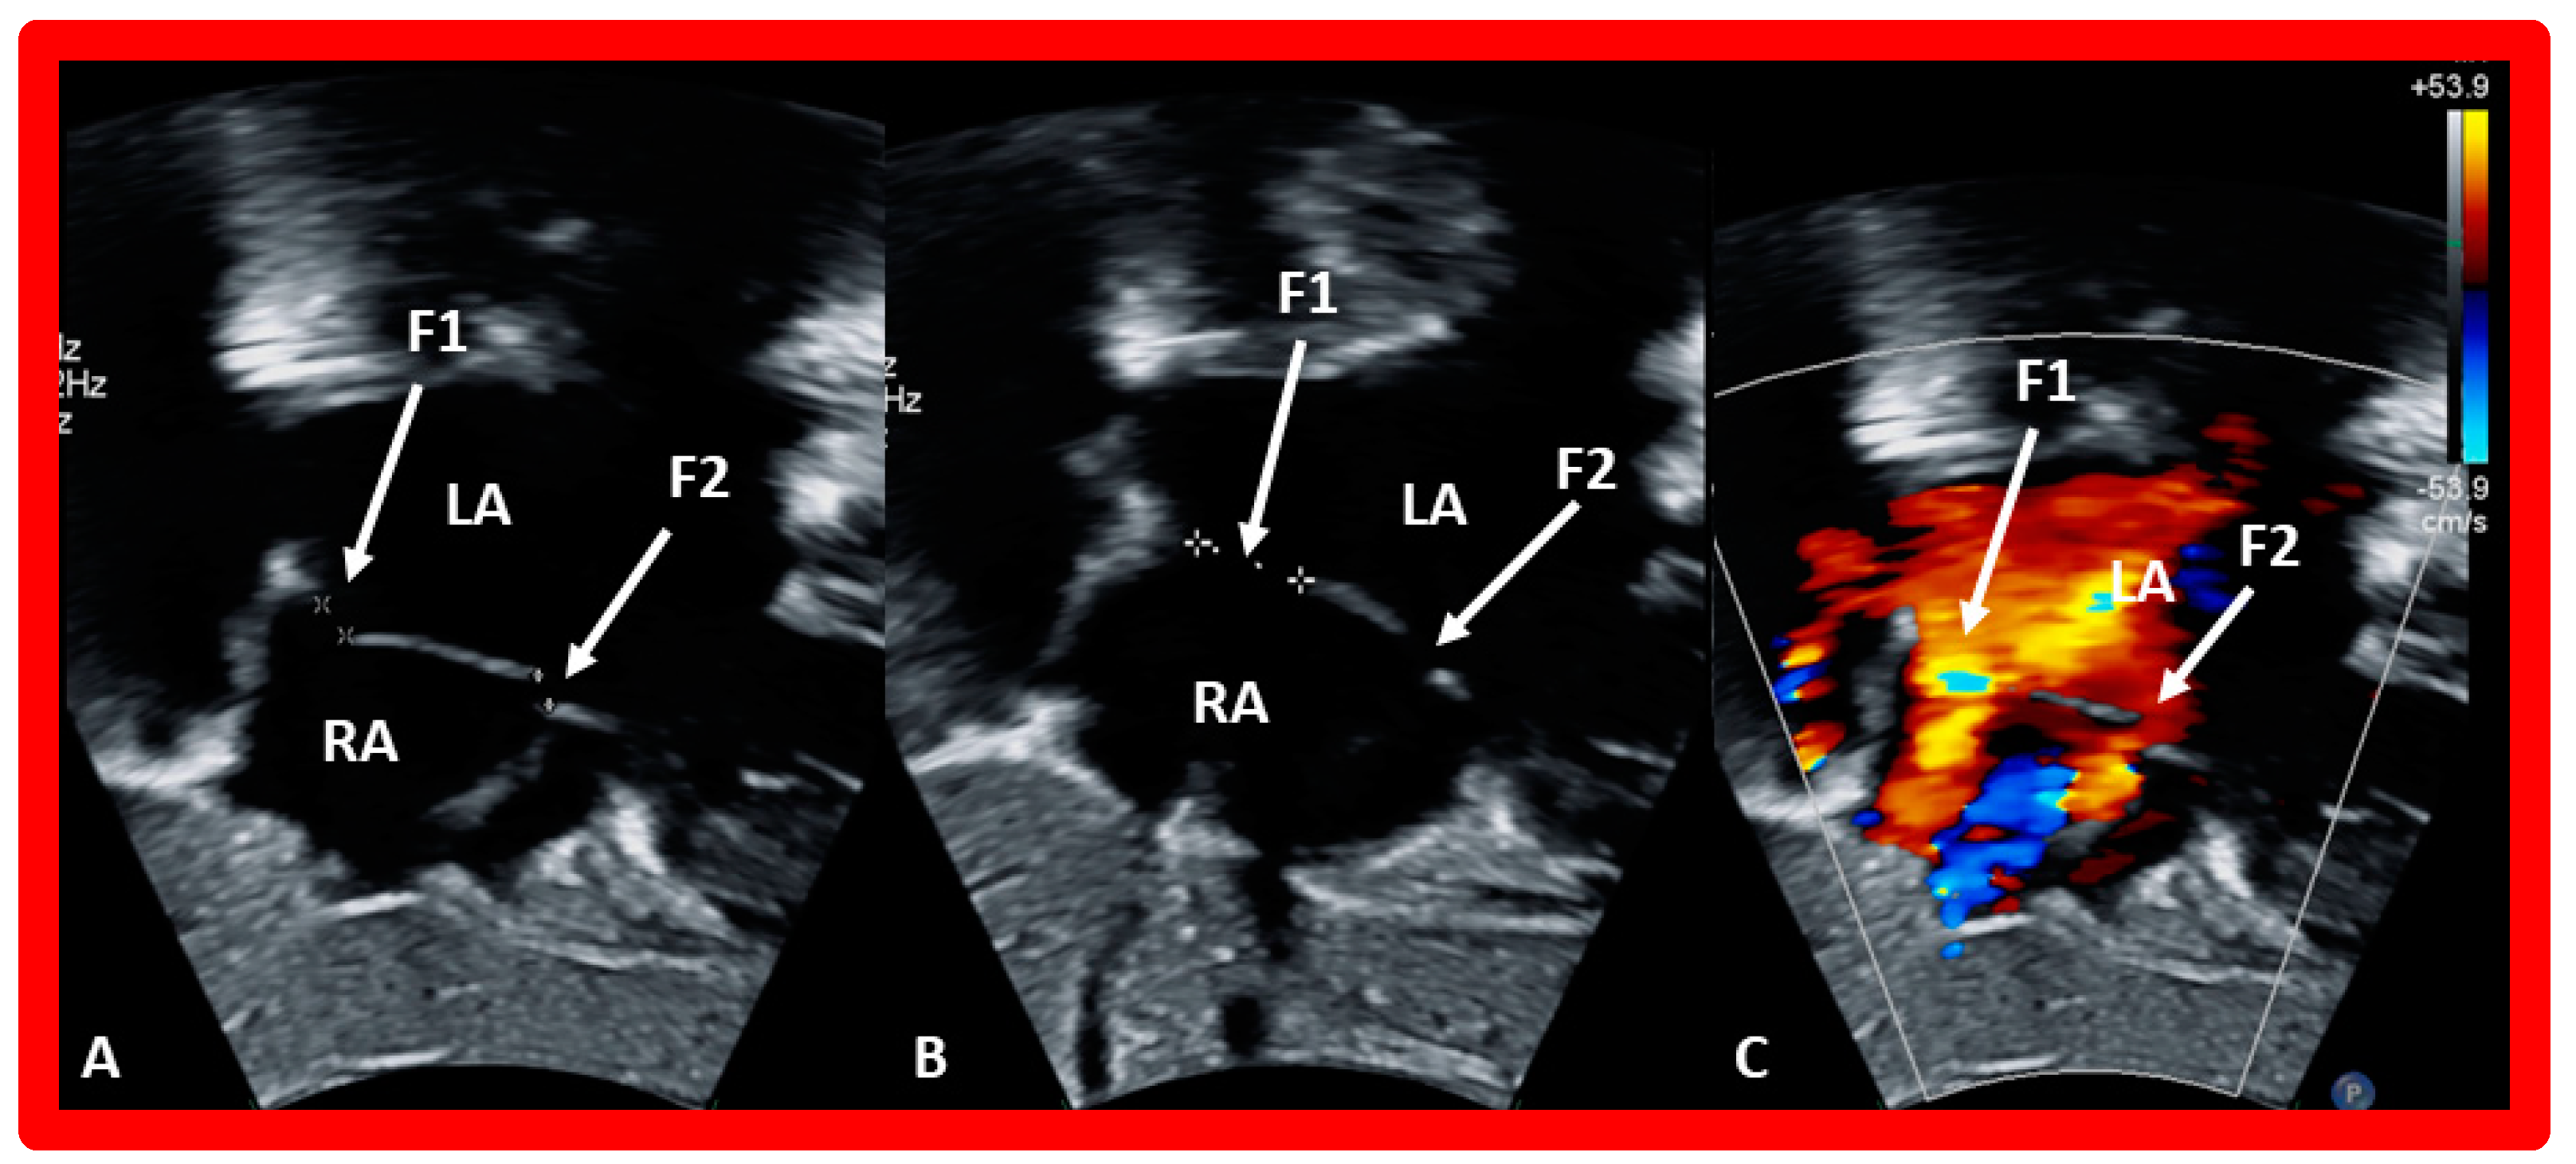

7. Balloon Sizing